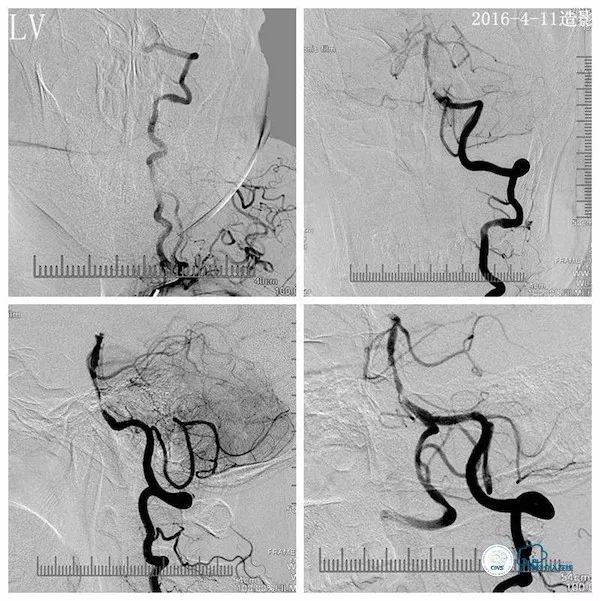

行头颅DSA示左椎动脉优势,左椎动脉V2段迂曲,基底动脉下段重度狭窄;左颈动脉造影见左后交通动脉开放,向双侧大脑后动脉及基底动脉远段代偿(2016-4-11,图3、4、5)。

图5